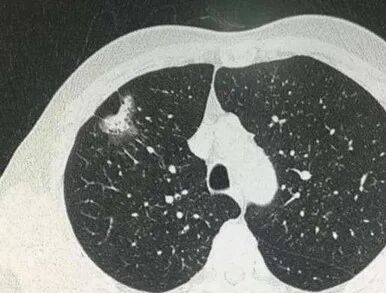

肺癌是发病率和死亡率增长最快 对人群健康和生命威胁最大的恶性肿瘤之一 换言之 发现得越早 治疗效果越好 我们与新华日报交汇点直播平台 江苏省科学传播中心合作 并邀请到了江苏省人民医院(南京医科大学第一附属医院)胸外科主任医师朱全 和我们聊一聊从肺结节到肺癌,如何实现精准诊疗? 专家简介 朱全,主任医师,江苏省人民医院胸外科副主任。中华医学会胸心血管外科学分会胸腔镜学组委员,中华医学会江苏省胸外科分会委员。 01 肺结节的性质 肺结节:< 3厘米 主要是指肺实质内单发或多发直径不超过 3 厘米 的圆形或类圆形结节影。不伴肺不张、肺钙化、肺门淋巴结肿大或胸膜渗出。 结节: <8毫米时称作亚厘米结节 <4毫米称作微结节 肿块: ≥ 3厘米 02 肺结节的分类 (1)实性结节 (2)半实性结节 (纯磨玻璃结节、混合磨玻璃结节) 实性结节 混合磨玻璃结节 结节分类 磨玻璃样结节 03 肺结节≠肺癌 •实性结节恶性率仅7% •部分实性结节恶性率为63% •纯磨玻璃结节恶性率为18% •>20 毫米的结节恶性率有80% 肺磨玻璃肺结节的演变 01胸部X光平片 对肺癌的漏诊率30% 不能发现肺小结节 02 薄层CT 5mm层厚已成为历史---导致误诊! 薄层CT比常规CT提供了7-10倍信息 (普通CT 60张对比 薄层CT 360-600张) 03 正确使用PET/CT • 能够评估结节的代谢活性。 • 对大于1厘米的实性结节有意义 • 对纯磨玻璃和混合性磨玻璃结节无效 • 不易区分炎症和结核 强调!!! 磨玻璃结节要经过随访 2-3个月的随访很重要 炎症的比例10% 随着时间会消失 肺结节CT影像AI辅助检测 外科手术的微创化 切口的微创化 全胸腔镜→3孔→2孔→单孔 肺切除范围的变化 非解剖性肺切除:楔形 解剖性肺切除:全肺切除、肺叶切除、肺段切除术、肺亚段切除术、肺次亚段切除术 肺段切除 早期肺癌的微创治疗外科手术的精准化 早期肺癌外科治疗中的规则: 保证肿瘤学效果是首要任务保留更多有功能的肺组织 三维CT支气管血管成像(3D-CTBA)肺结节与早期肺癌